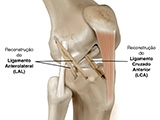

Reconstrução Ligamentar

Tratamento cirúrgico para restaurar a estabilidade do joelho.